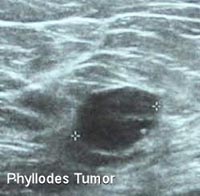

- Siêu âm: bướu cho phản âm đồng nhất, ngoài ra còn thấy hình ảnh các nang nhỏ ở ngoại vi có chứa dịch. Trên siêu âm cũng khó phân biệt bướu này với bướu sợi tuyến, ngoài một số gợi ý như có nang trong bướu, hình ảnh tăng sinh mạch máu.